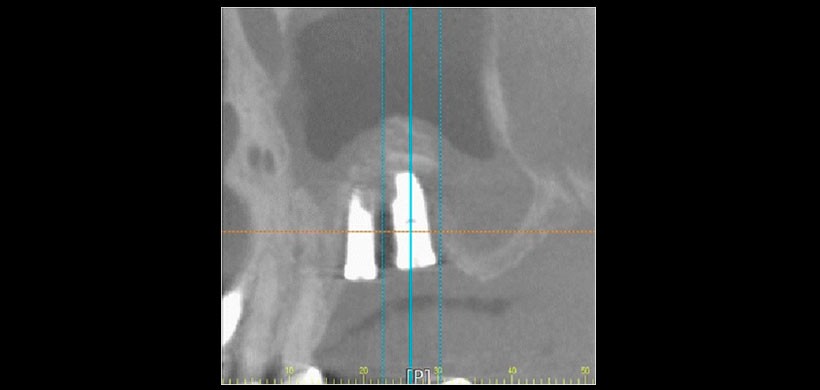

Figura 1: a) Vista panorámica preoperatoria y b) Vista de la tomografía computarizada cone beam (CBCT)